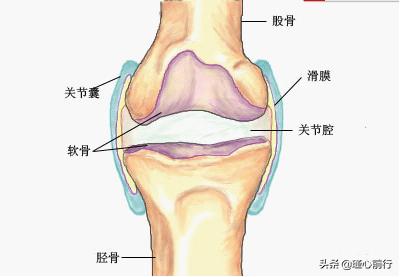

膝盖滑膜炎应该叫膝关节滑膜炎,滑膜炎是滑膜组织损伤引起关节液的分泌和吸收不平衡,这种不平衡主要有两种形态,

一种是最常见的是分泌多吸收少形成关节有积液,常见症状为疼痛症状明显或肿胀。

一种是分必少吸收多形成关节腔里关节液少,常见症状为活动或受力时有症状或关节有响声。

滑膜炎简单说就是关节腔内的无菌性炎症,滑膜炎发病部位较高的是膝关节和髋关节,关节腔内关节液分泌吸收不平衡导致滑膜炎,走路咯吱响是由于关节积液失去了润滑作用,骨头磨骨头发出的异响。发病原因多为损伤、劳损、受凉等,完全可以通过外用膏药痊愈。凤延堂推荐使用中医膏药贴敷受损关节,使药力直达病灶,修复疏通关节腔内微循环,使积液分泌吸收达到平衡状态,修复受损软组织,最终达到痊愈的效果。通过我们凤延堂的临床经验来看,这类病症有全年龄、范围广、恢复慢、易复发等特点,而中医膏药有受用范围广、恢复基础牢、治愈率高等特点,特别适合担心手术后遗症、陈年老伤、从事职业滑膜炎易反复发作的人群。同时建议已经患有滑膜炎的人注意保护自己的各个关节,秋冬季节需要加强关节部位的保暖,夏季避免长时间吹空调等,这样有利于关节的自我修复。